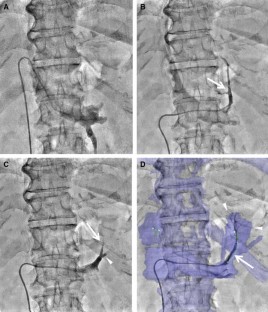

Fig. 3